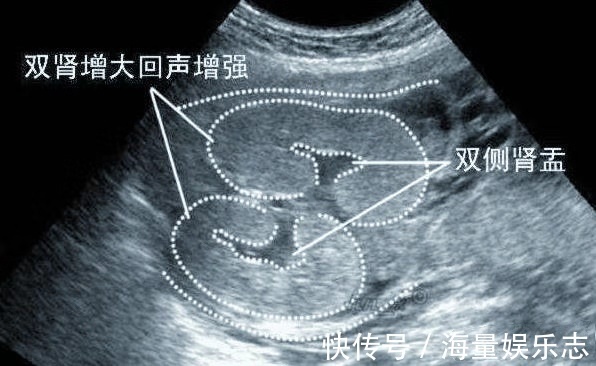

那么,什么就叫做双肾盂分离,是什么原因导致,胎儿双肾盂分离,真的预示胎儿性别吗?今天美妈就来给大家梳理一下。胎儿双肾盂分离的原因有哪些?所谓的肾盂,是指肾与输尿管的连接处;而肾盂分离,就是肾脏的尿液无法正常地流入膀胱。当尿液积存到一定的时候,就会出现肾盂分离。胎儿肾盂分离的原因有两个,一个是由于输尿管的一部分狭窄而导致尿液流动停滞,另一个是积存在膀胱中的尿液朝肾脏逆流而造成。

怎么判断肾盂分离是否正常?胎儿双肾盂分离多半发在孕中期与孕晚期。孕妈听到胎宝宝肾盂分离或许有会很焦虑,其实不必过于担心。胎儿肾脏轻度分离是很常见的,据统计显示,100个胎儿之中就有一个胎儿会出现肾盂轻度分离的情况,而且大部分会随着孕周增长而逐渐消失。正常来说,肾盂分离<10mm,为生理性,不必特别处理,孕妈定期检查就好。但是怀孕30周后,肾盂分离≥10mm,则可能要考虑肾积水了,一个小时后需要再进一步确认,检查结果还是一样的话,那医生就要给胎儿做相关的检查,必要时进行治疗,据说这种情况600-800个胎儿之中有1个,而且有99?小宝宝在出生后可治好。像题主这样,孕早期就有,孕晚期还没消失而且肾盂分离≥10mm,则要跟医生沟通一下了。

孕期胎儿双肾盂分离,多半怀“小公子”?确实,与女宝宝相比,男宝宝发生双肾盂分离概率比女宝宝高4-5倍!这是由于男宝宝的尿道较长,膀胱内压更高,比女宝宝更容易憋尿,因而更容易引发双肾分离。虽然概率较大,但还有40?机会生小棉袄,所以不要像小樱那样就此轻易下结论!